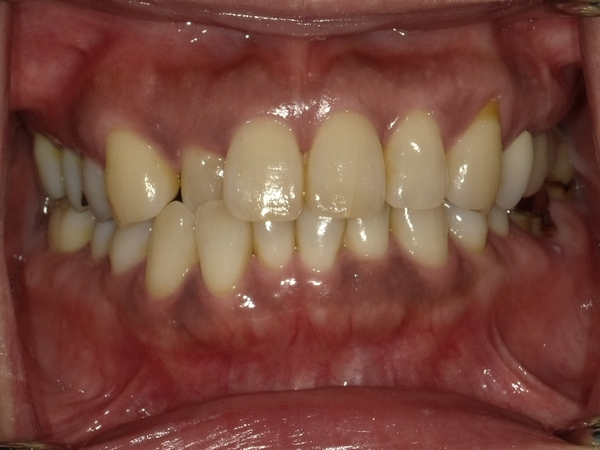

〇ご相談内容:上の前歯が内側に入っている、下の歯のがたつきが気になる〇矯正の種類:マウスピース型矯正「インビザライン」〇治療期間:14週間(約3ヵ月)〇治療費用:44万円(税込)